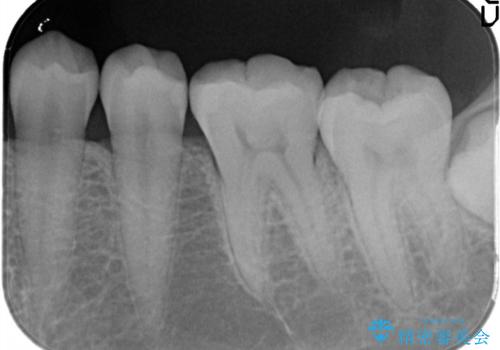

- 金属の詰め物がはずれてしまったので、精度の良いセラミックをいれたいのとのこと来院されました。

セラミックインレーにて治療することとなりました。

拡大鏡を使用して精度の高いインレーを装着しました。